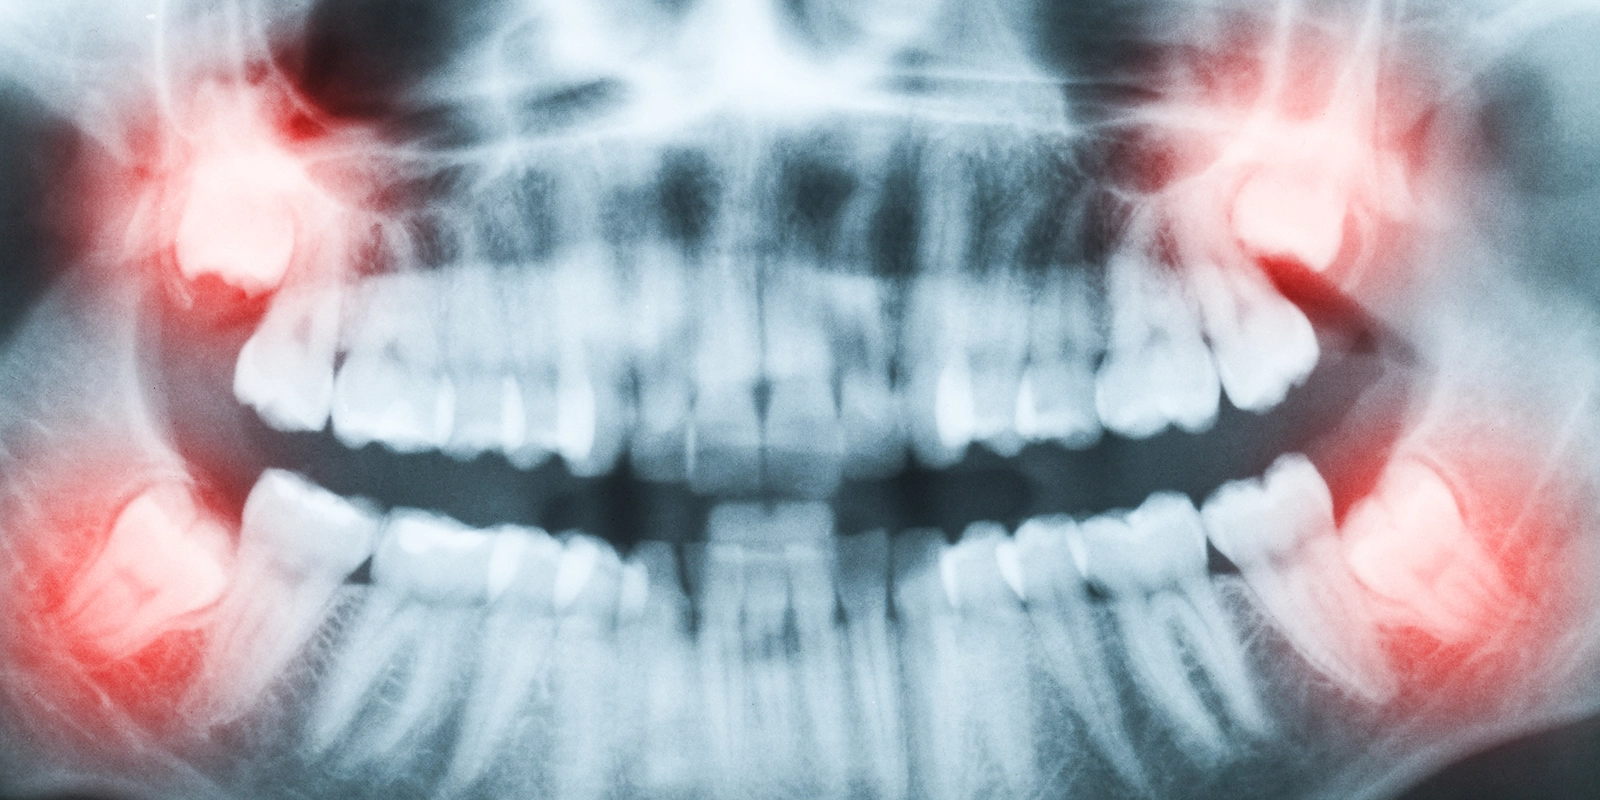

口が開きにくい親知らず抜歯 -

親知らず抜歯

腫れて痛い、

口が開きにくい

親知らず抜歯について

親知らずとは、正確には第三大臼歯のことで、10代後半〜20代で生えてくることが多いです。上下左右に1本ずつ、合計4本あります。

真っ直ぐに生える方もいれば、顎のサイズから生えるスペースが無くて横向きに生えてしまう方もいます。先天的に無い方もいます。

真っ直ぐ生えていて、歯ブラシが届くような状態であればセルフケア可能ですので、温存しても良いと考えられます。逆に真っ直ぐ生えていてもケアができていなかったり、横向きの親知らず、頻繁に腫れて痛みを生じるような親知らずは、抜歯適応と考えて良いでしょう。

親知らず抜歯が必要なケース

親知らず抜歯の難易度

親知らずの難易度の分類にWinters分類というのがあります。一般的に親知らずが埋もれている位置が深いほど、また親知らずを覆っている骨が多いほど、難易度は高くなります。難易度が上がるほど、術中、術後の痛みや、術後の腫れの程度は大きくなる傾向にあります。

CT検査による診断

全ての症例に必要な訳ではありません。下顎には下歯槽神経(三叉神経の第3枝)という重要な神経が親知らずの根元付近を走行しており、また上顎には上顎洞(副鼻腔の一つ)という鼻の穴と連続している空洞があります。抜歯後に神経を損傷して麻痺症状を生じたり、上顎洞と交通すると鼻血や口腔内から鼻の方に水が漏れるなどの偶発症を生じる場合があります。

パノラマやデンタルという普段使うX線画像検査は平面的な画像のため、重要な解剖学的ランドマークと治療目的の歯の三次元的な位置関係は正確には分かりません。CT撮影により重要な神経との位置関係が正確に分かるため、手術の際にどの部分を触るのが安全なのか、手術計画の立案に役立ちます。

特に下顎の親知らずの根と下歯槽神経(三叉神経第3枝)はくっついていたり近接していることがあります。抜歯時にその神経を損傷してしまうと、抜歯した側の下唇や顎先、舌の側面が痺れたり、感覚が鈍くなることがあります。

CTを撮影することで予め抜歯の難易度や、ある程度の神経損傷の可能性が分かります。リスクが高い場合は抜歯を見送ることもあります。